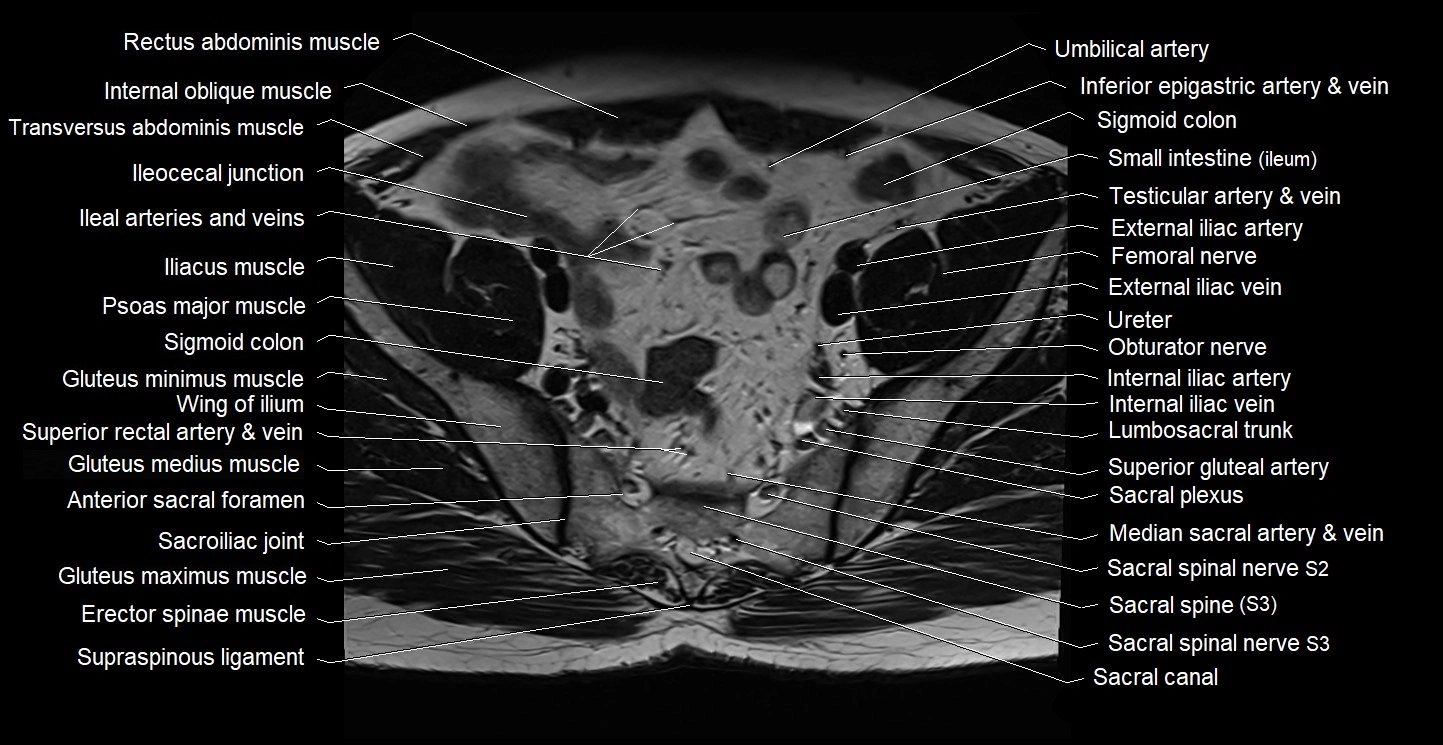

- Anterior sacral foramina

- Sacral canal

- Sacral plexus

- Sacroiliac joint